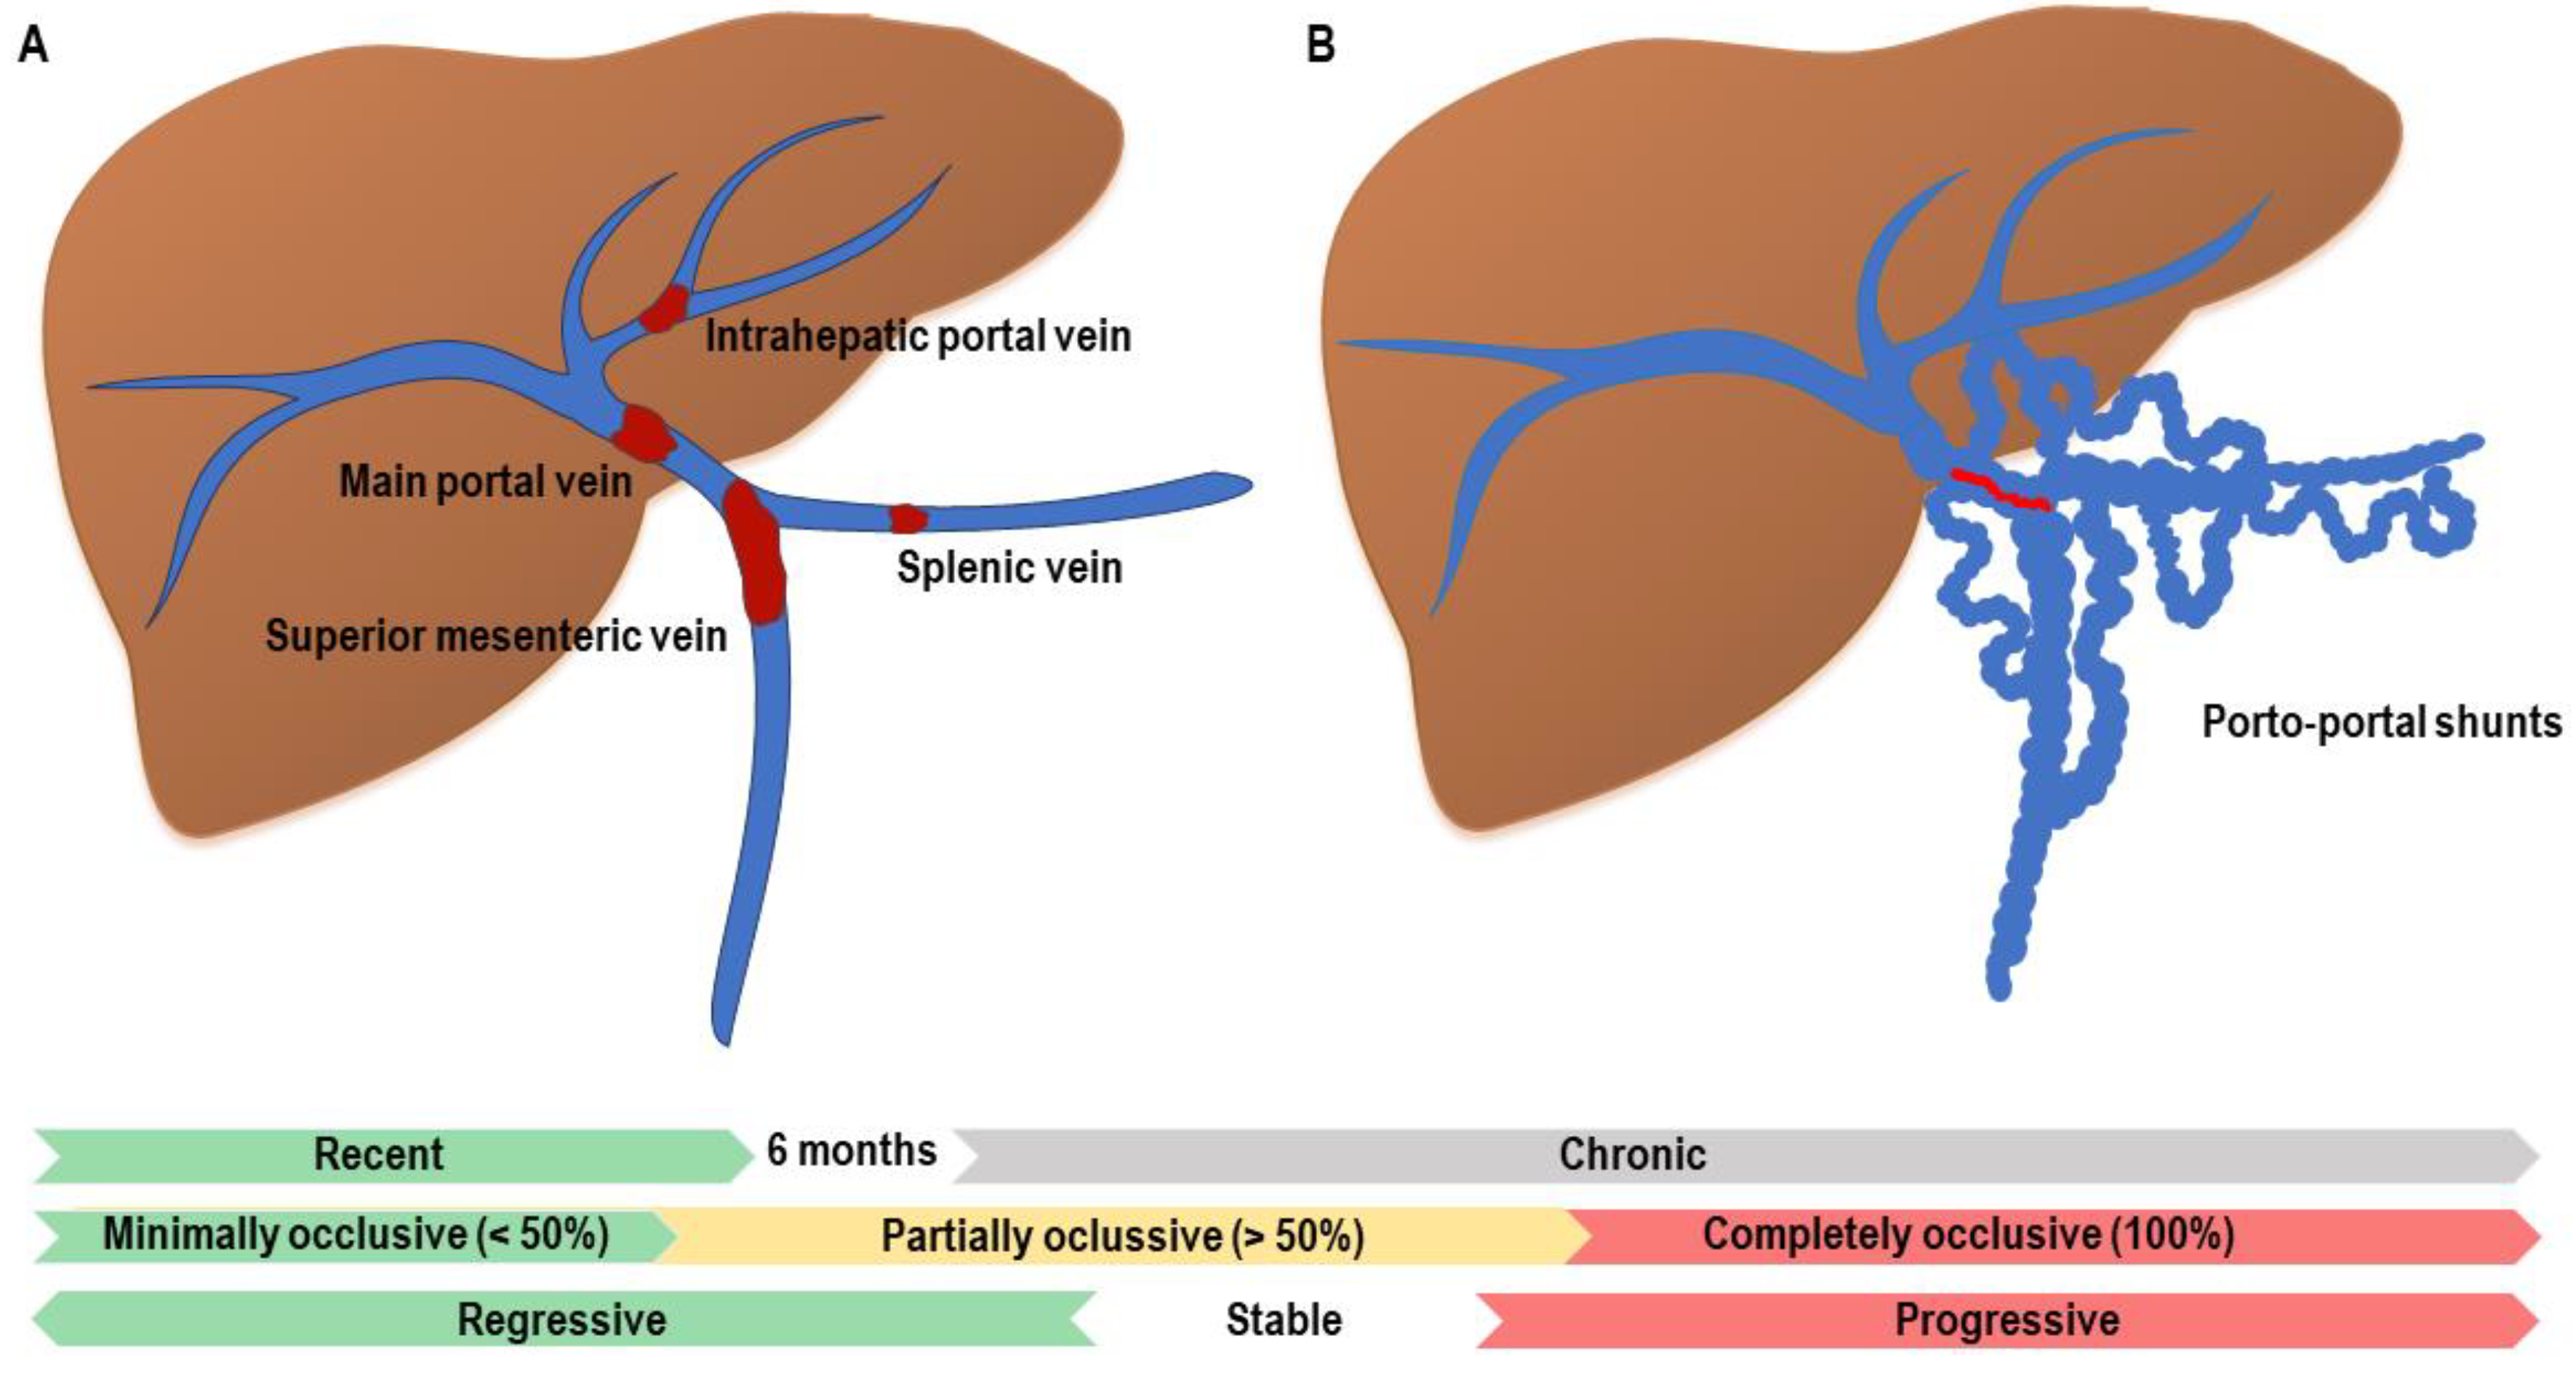

JCM Free Full Text Portal Vein Thrombosis In The Setting Of

JCM Free Full Text Portal Vein Thrombosis In The Setting Of